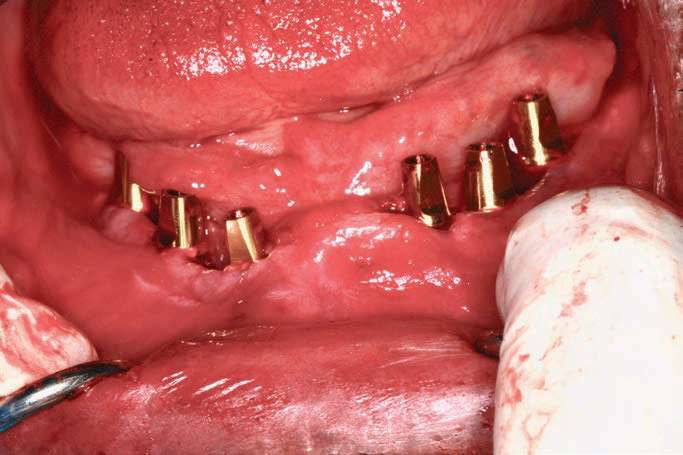

BioHorizons implants were selected in order to increase bone-implant contact, as the threads are designed to optimize bone contact as well as utilize Laser-Lok technology (BioHorizons) to hold the hemidesmosomes of the tissue so that the tissues would be less friable and provide for better tissue dynamics. Upon implant placement, a Piezo surgical device (PIEZOSURGERY by Mectron) was used to remove sharp lips of bone as the implants were countersunk by design. The PIEZOSURGERY by Mectron works by using micro-vibrations to cut bone while minimizing soft-tissue trauma. The device and its internal irrigation provides an almost blood-free foundation while cleaning around the implants and removing unwanted tissues. The cutting is micrometric, and the micro-vibrations not only cut bone but help collect bone particles to be used in the defects around the implants so the autogenous shavings can be placed adjacent to the exposed threads or fenestrations[14] (Figure 7).

The BioHorizons implants were placed with a good A-P spread, and the bone in the anterior mandible was left in case it was needed at the uncovery appointment (Figure 8). At the uncovery visit, the LightScalpel laser was used to perform a trephine of the posterior implants by placing the surgical guide, marking the osteotomy sites with a Dr. Thompson’s marking stick, and (using a super-pulsed 2W setting) to gently remove the cuff of tissue over the implants (Figure 9). In the anterior mandible, a full-thickness flap was done, and the remaining bone was removed with the PIEZOSURGERY device (Figure 10). The peri-mucosal healing abutments were placed, and a soft-tissue conditioner was placed in the lower denture (Figure 11). After one month of healing, the patient was ready for impressions (Figure 12).